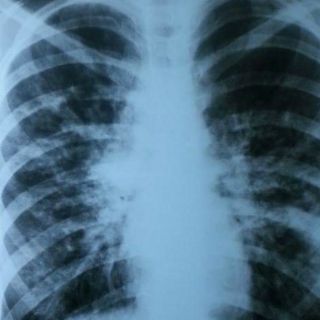

Explicó que esta enfermedad aparece en los primeros meses de vida y se caracteriza por tos crónica, respiración agitada, infecciones pulmonares recurrentes y por evacuaciones abundantes, frecuentes, grasosas y de muy mal olor.

Guadalupe Campoy Ruy Sánchez, directora de la Asociación Mexicana de Fibrosis Quística, explicó que 95 por ciento de los pacientes diagnosticados con esta enfermedad mueren a causa de problemas pulmonares crónicos, debido a que producen moco anormal que bloquea los conductos respiratorios y propicia infección crónica.